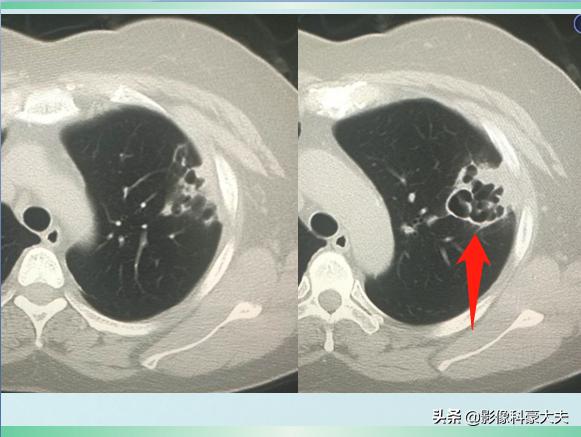

我们先不公布答案,继续看她治疗10天后的复查CT:

对比前两次片子,黑色空洞影变得更大了,周围的白色炎症斑片影吸收好转了。

这是一种什么细菌呢?为什么会短时间引起肺组织坏死空洞?经过实验室培养,医生们找到了真相——肺炎克雷伯杆菌。